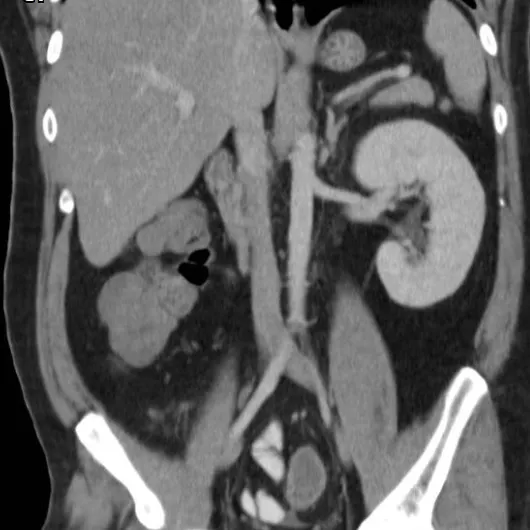

Injúria Renal Aguda (revisão Lancet 2025)